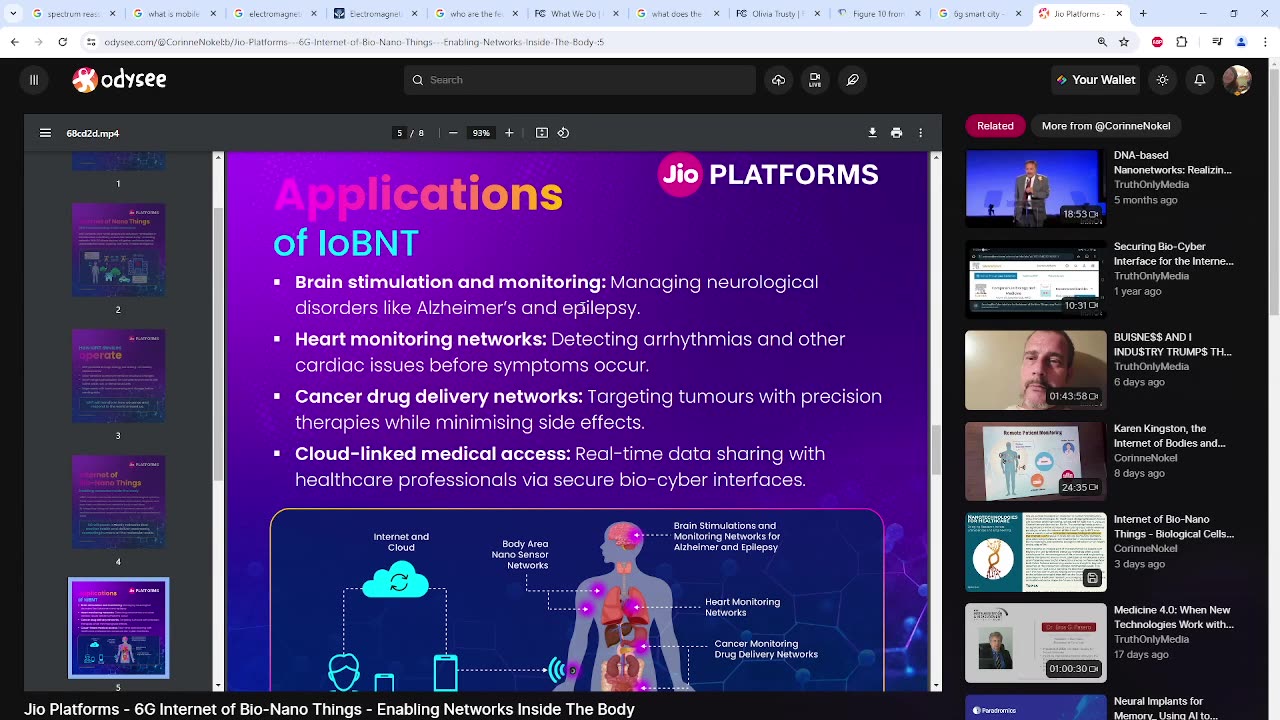

BROOKLYN 6G Summit &loBNT Connectivity